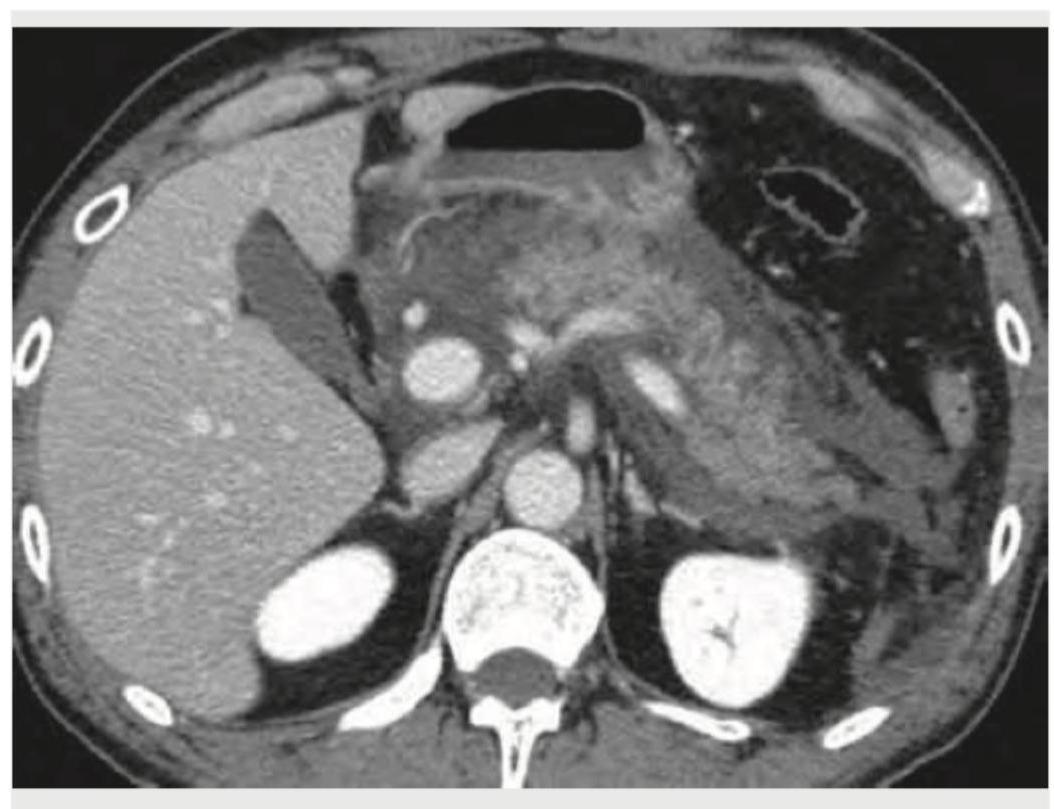

The given CT abdomen shows:

Explanation: ***Acute pancreatitis*** - The CT image reveals signs of acute pancreatitis, characterized by diffuse **enlargement and blurring of the pancreatic margins**, along with **peripancreatic fat stranding** and **fluid collections**, particularly around the tail of the pancreas. - These findings are indicative of **inflammation and edema** within and around the pancreas, consistent with an acute inflammatory process. *Acute hepatitis* - Acute hepatitis typically presents with **diffuse liver enlargement**, **edema**, and sometimes periportal edema or gallbladder wall thickening, which are not the primary findings here. - While the liver appears somewhat enlarged and heterogeneous, the extensive peripancreatic inflammation and fluid collections point away from primary liver pathology. *Acute cholecystitis* - Acute cholecystitis is characterized by **gallbladder wall thickening**, **pericholecystic fluid**, and sometimes gallstones, which are not visible or prominent enough to be the primary diagnosis in this image. - The pathology seen is clearly centered around the pancreas, not the gallbladder. *Pseudo-pancreatic cyst* - A pancreatic pseudocyst would appear as a **well-defined, encapsulated fluid collection**, often occurring weeks after an episode of acute pancreatitis. - In this image, the fluid collections are **ill-defined** and appear to be part of an acute inflammatory process with fat stranding rather than a mature, encapsulated pseudocyst.